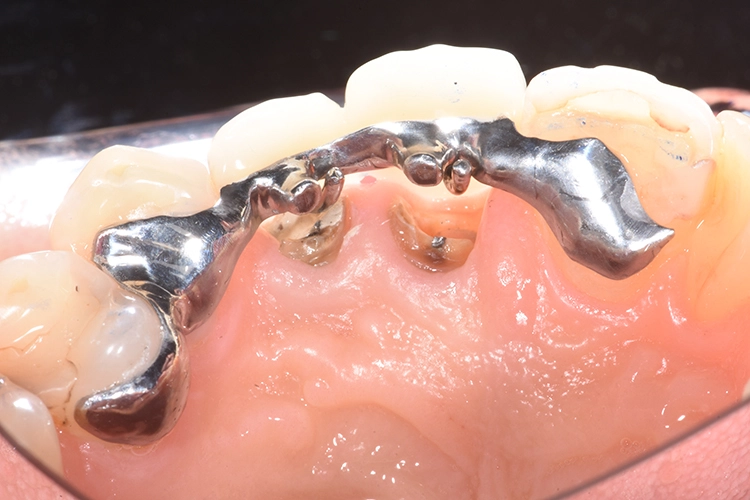

Ihr wurden die verschiedenen Behandlungsmöglichkeiten erklärt. Die Patientin wünschte sich den Erhalt der eigenen Zähne. Aufgrund der Breite der Lücke und schwierig zu schienender Situation entschieden wir uns für eine kieferorthopädische Extrusion der beiden Wurzelreste.

Dr. Blume